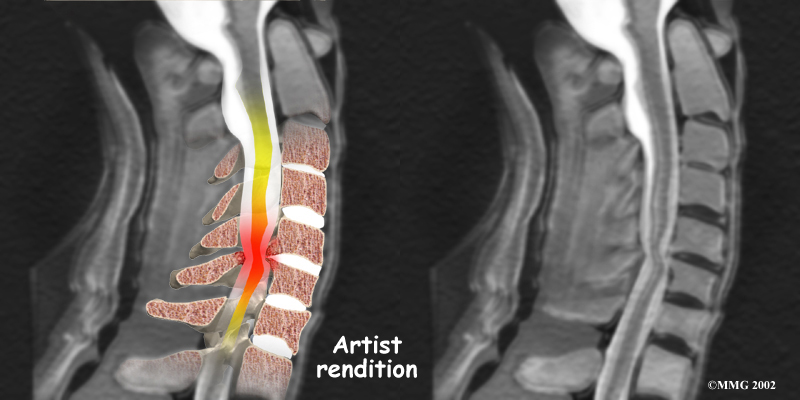

The nucleus may push through the weakened and torn annulus and into the spinal canal. This is called a herniated or ruptured disc. The disc material that squeezes out can press against the spinal nerves. The disc also emits enzymes and chemicals that produce inflammation. The combination of pressure on the nerves and inflammation caused by the chemicals released from the disc cause pain.

- Herniated Disc: Heavy, repetitive bending, twisting, and lifting can place extra pressure on the shock-absorbing nucleus of the disc. If great enough, this increased pressure can injure the annulus (the tough, outer ring of the disc). If the annulus ruptures or tears, the material in the nucleus can squeeze out of the disc. This is called a herniation. Although daily activities may cause the nucleus to press against the annulus, the body is normally able to withstand these pressures. However, as the annulus ages, it tends to crack and tear. It is repaired with scar tissue. Over time, the annulus becomes weakened, and the disc can more easily herniate through the damaged annulus.

If the herniated disc material presses against a nerve root it can cause pain, numbness, and weakness in the area the nerve supplies. This condition is called cervical radiculopathy (mentioned earlier). And any time the herniated nucleus contacts tissues outside the damaged annulus, it releases chemicals that cause inflammation and pain. If the nucleus herniates completely through the annulus, it may squeeze against the spinal cord. This causes a condition that is even more serious because it affects all the nerves of the spinal cord. This condition is called cervical myelopathy.

The magnetic resonance imaging (MRI) scan uses magnetic waves to create pictures of the cervical spine in slices. The MRI scan shows the cervical spine bones, as well as the soft tissue structures such as the discs, joints, and nerves.

MRI scans are painless and don't require needles or dye. The MRI scan has become the most common test to look at the cervical spine after X-rays have been taken.